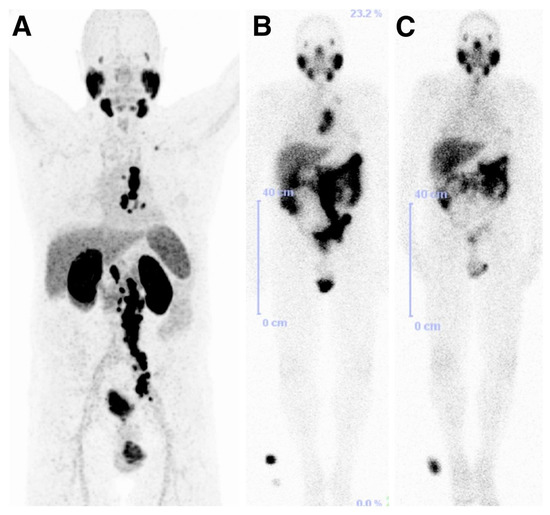

An exploratory investigational new drug application (IND) was implemented to bring the compounds MIP-1404 and MIP-1405 which been developed by the group at Molecular Insight Pharmaceuticals (MIP), and labeled with 99mTc, into the clinic. Vallabhajosula et al. [143], reported the comparison of the pharmacokinetics, biodistribution, and tumor uptake of 99mTc-MIP-1404 and 99mTc-MIP-1405 in 6 healthy men and 6 men with radiographic evidence of metastatic prostate cancer. SPECT imaging was performed between 3 and 4 h after injection of the radiotracers (Figure 18). Both radiotracers showed fast blood clearance persistent uptake in the salivary, lacrimal, and parotid glands. They localized in bone and lymph node lesions as early as 1 h. Because of the lower urinary activity of 99mTc-MIP-1404 (7%) compared to 99mTc-MIP-1405 (26%), a clear advantage for detecting prostate cancer in the gland and pelvis at early stages of the disease is indicated for this compound. 99mTc-MIP-1404 was selected for phase II studies to determine sensitivity and specificity to detect prostate cancer in high-risk patients. Furthermore, the development and optimization of a “cold” kit for the preparation of 99mTc-MIP-1404 using generator eluted pertechnetate has also been reported [144].

Figure 18.

Tumor uptake of 99mTc-MIP-1404 (A) or 99mTc-MIP-1405 (B) at 4 h in patient with metastatic prostate cancer, compared with that of standard bone scan (C). Images also show uptake of radiotracer in normal parotid and salivary glands. Ant = anterior; Post = posterior (Reprinted with permission of [143]).